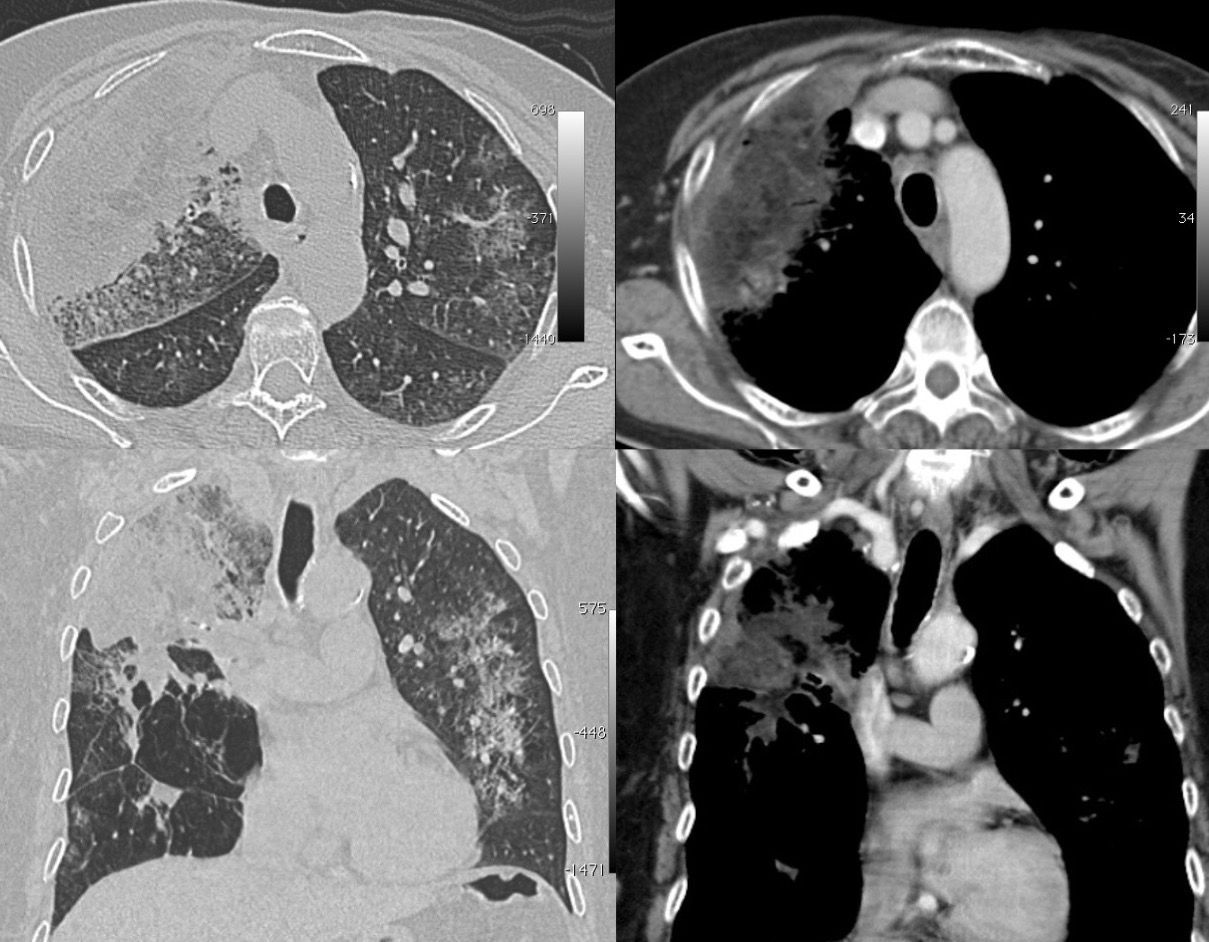

Case 29: The Slow Long Burn of Sarcoidosis Paid Members Public

The changing patterns of disease over 16 1/2 years in this patient with biopsy proven sarcoidosis